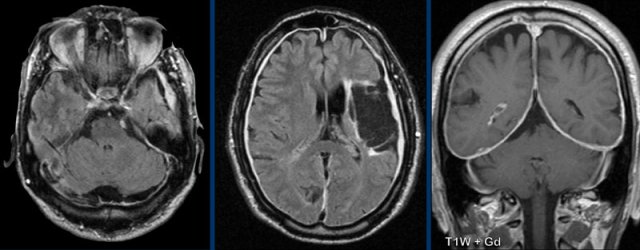

These images are of a 55-year old immunocompromised patient, who presented with cognitive complaints and headache.

Images

FLAIR shows non-supressed enhancing CSF in the subarachnoid

space.

Look along the cerebellar foliae, these are hyperintense on FLAIR (black arrowheads).

There is faint leptomeningeal enhancement (yellow arrowhead).

Furthermore there is high FLAIR signal at the

perivascular spaces in the semioval centre with enhancement.

Conclusion

This turned

out to be cryptococcal meningitis.

The spread

along the perivascular spaces in an immunocompromised patient is suggestive.

Sometimes in these patients there are also pseudocysts.